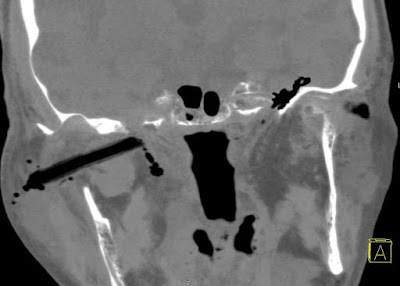

Szerző: admin | jún 23, 2011 | Foreign body, Paranasal sinuses, Trauma

Fall into flower bed.The removed foreign body proved to be chrysanthemum stalk.Thanks to Dr Szukits for the reconstructions.